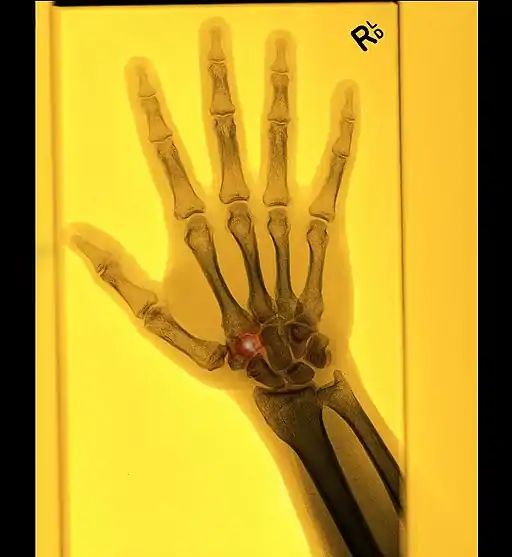

- ↑ Mettler FA Jr, Huda W, Yoshizumi TT & Mahesh M, 2008. Effective doses in radiology and diagnostic nuclear medicine: A catalog. Radiology, 248:254-63.